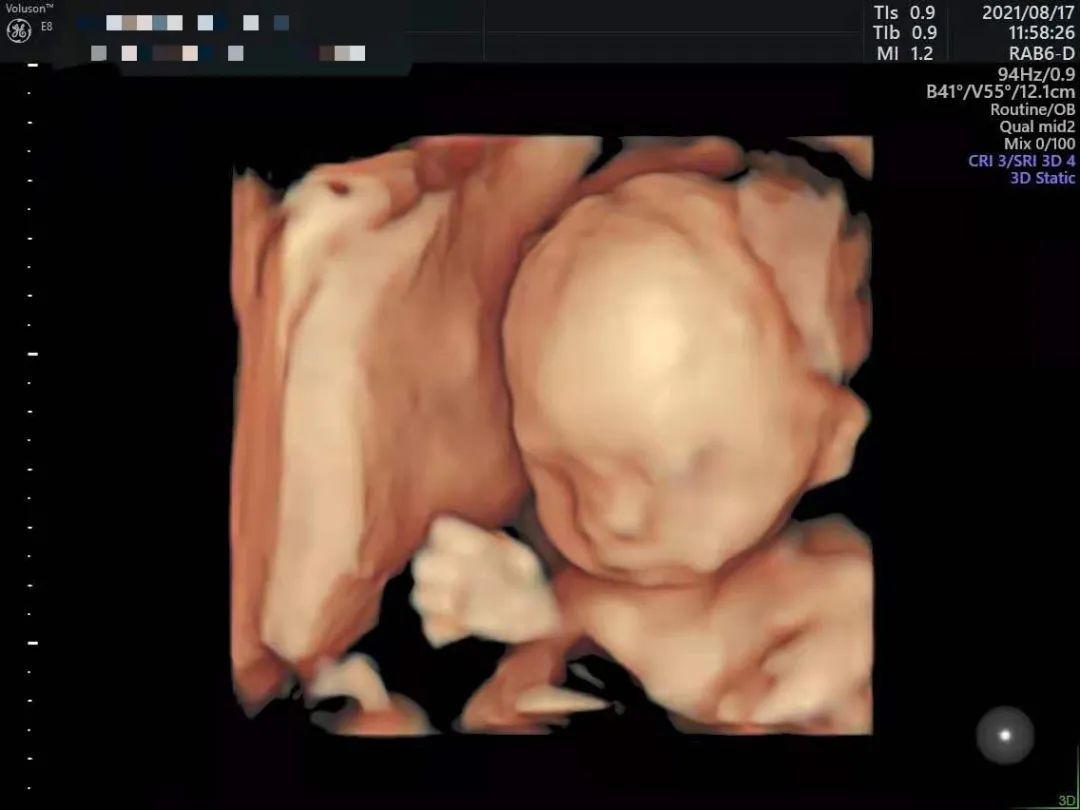

通过四维可以“看”到什么